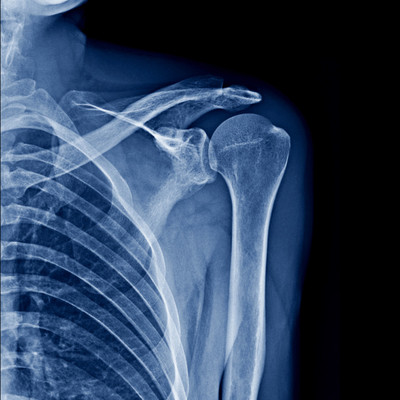

On-Site Digital X-Ray

3.) On-Site Digital X-Rays

Our on-site digital X-ray saves you the hassle of multiple appointments. This allows us to assess your injuries and begin treatment the same day.

If further imaging—like an MRI or CT scan—is needed, or a referral to a specialist is appropriate, we can coordinate that directly from our office.